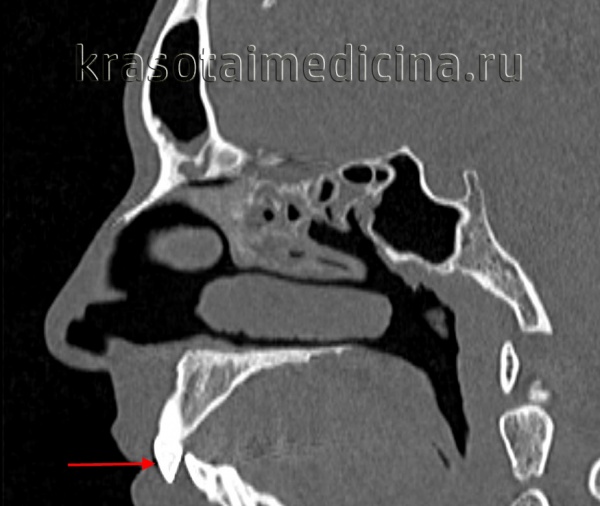

Дистальное положение челюстей на телерентгенограмме

- Компьютерная томография или 3D-проекция черепа. По ней можно оценить важные показатели для ортодонтического лечения: клиническую форму прикуса, размер и положение челюстей. Положение и соотношение зубов в костной ткани и ее объемы. Состояние и положение головки височно-нижнечелюстного сустава. Трехмерная модель черепа дает более точное представление о положении зубов и челюстей, чем классических 2D-снимок черепа в боковой проекции.

КТ черепа (3D-рендеринг). Прогнатический прикус, зубы верхней челюсти (красная стрелка) выстоят кпереди, отсутствует контакт резцовых краев при смыкании.

КТ черепа. Прогнатический прикус, зубы верхней челюсти (красная стрелка) выстоят кпереди (этот же пациент).